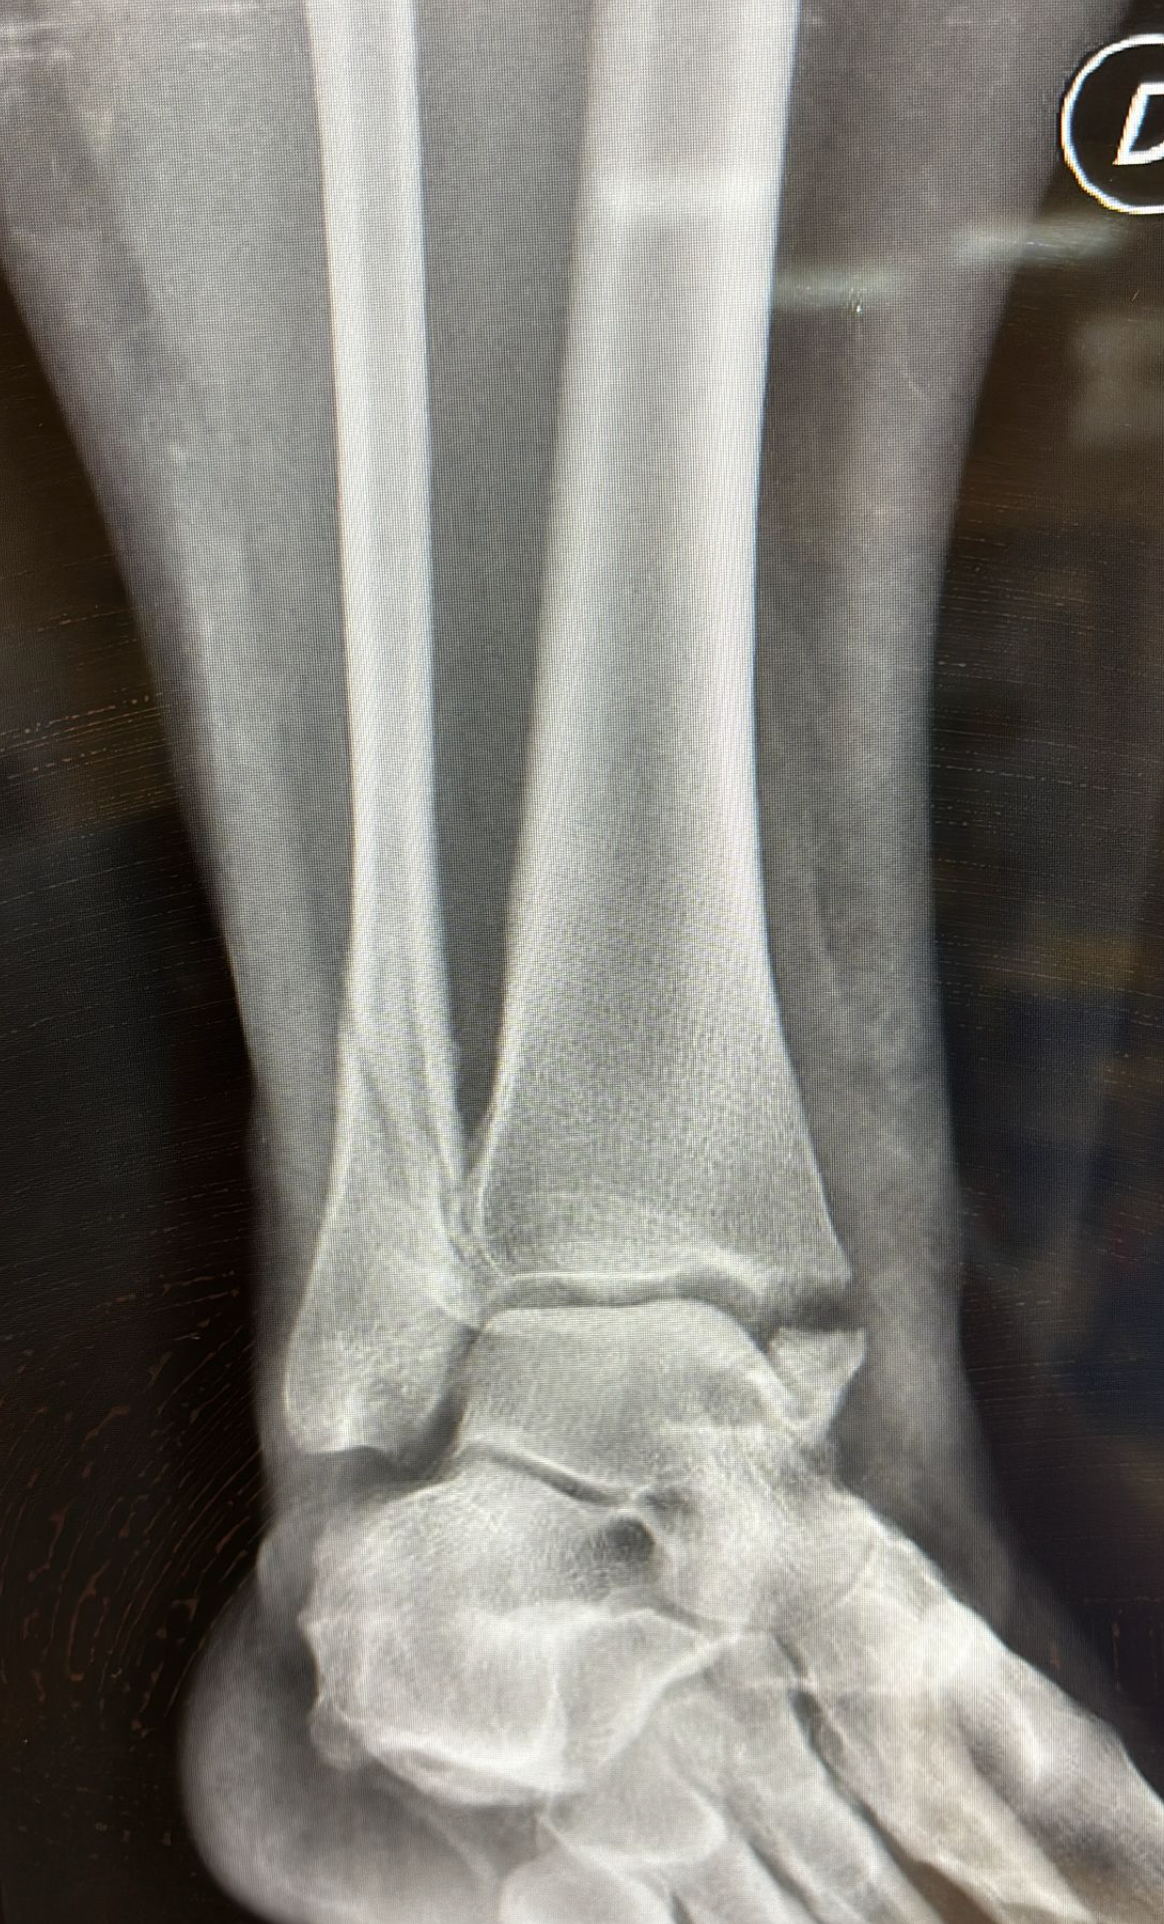

It is not always easy to determine whether ankle pain is caused by a sprain or a fracture. For this reason, it is advisable to visit an emergency room and undergo an X-ray.

- After 60 days, the cast is removed, X-rays are performed, and a walker boot is provided. Rehabilitation begins, with gradual weight-bearing of about 50 kg for another 30 days.